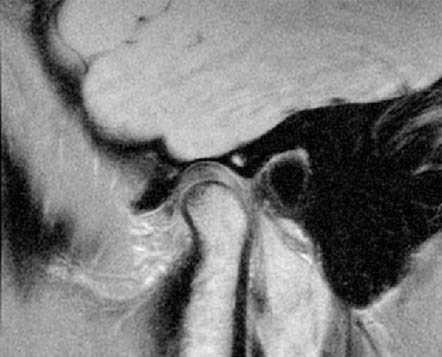

Во время проведения УЗИ на экране монитора во всех случаях хорошо визуализировались головка нижней челюсти, суставной диск, определялось его патологическое положение, измерялась степень смещения диска на всех этапах исследования. Следует отметить, что задние отделы суставного диска и головки нижней челюсти не всегда достаточно хорошо визуализировались, но, поскольку у всех наших пациентов наблюдалось переднее смещение суставного диска, контроль за нормализацией его положения был всегда возможен. После нескольких атропункций у 56 человек положение суставного диска нормализовалось, что подтверждается результатами УЗИ (рис. 2). Рисунок 2. Репозиция суставного диска ВНЧС у пациентов с невправляемым его смещением с помощью метода гидравлического прессинга под контролем УЗИ (пример 1). а — суставной диск смещен кпереди и деформирован. Рисунок 2. Репозиция суставного диска ВНЧС у пациентов с невправляемым его смещением с помощью метода гидравлического прессинга под контролем УЗИ (пример 1). б — после артропункции и гидравлической репозиции: суставной диск расправлен и равномерно распределен над головкой нижней челюсти. Рисунок 2. Репозиция суставного диска ВНЧС у пациентов с невправляемым его смещением с помощью метода гидравлического прессинга под контролем УЗИ (пример 2). а — суставной диск смещен кпереди и деформирован. Рисунок 2. Репозиция суставного диска ВНЧС у пациентов с невправляемым его смещением с помощью метода гидравлического прессинга под контролем УЗИ (пример 2). б — после артропункции и гидравлической репозиции: суставной диск расправлен и равномерно распределен над головкой нижней челюсти.